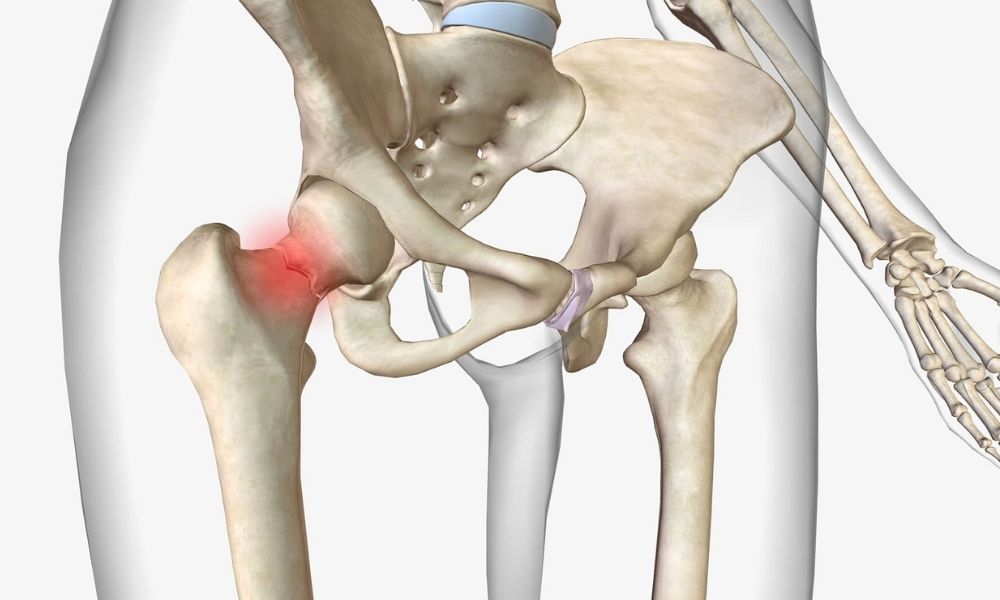

Uyluk kemiğinin boyun kısmının öne doğru açılı olmasıdır. Femoral anteversiyon genellikle çocukluk döneminde fark edilir. Ayakların içe dönük basmasına neden olabilir. Yürüyüş bozuklukları görülebilir. Genetik faktörler etkili olabilir. Çoğu zaman kendiliğinden düzelir. Bazı durumlarda fizik tedavi gerekebilir. Nadir olarak cerrahi müdahale uygulanır. Teşhis için ortopedi uzmanı değerlendirme yapar.

Femoral anteversiyon tanısında yürüme analizi önemli bir araçtır. Hastanın yürüyüşü özel kameralar ve sensörlerle kaydedilerek detaylı incelenir. Bu analiz sayesinde kalça rotasyonu ve içe basma derecesi ölçülür. Kesin tanı için görüntüleme yöntemleri de devreye girer. MR ve BT taramalarıyla femur kemiğinin kalçaya göre açısı belirlenir. Normal açının 10–15 derece olması beklenir; 20 derece üzeri anormal kabul edilir.

Görüntüleme sonuçlarıyla femur başı ve boynu arasındaki açılar ölçülür. Bu ölçümler anteversiyonun şiddetini ortaya koyar. Hafif, orta veya ileri düzey olarak sınıflandırılır. Diğer yürüme bozukluklarıyla karışmaması için ayırıcı tanı yapılır. Kalça çıkığı, serebral palsi ya da tibial torsiyon gibi durumlar dışlanmalıdır. Bu nedenle kapsamlı değerlendirme gerekir.